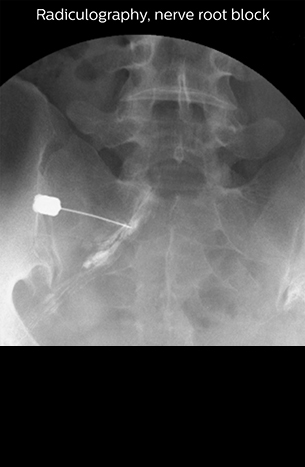

“Before NerveVIEW, diagnosis by MRI alone was sometimes difficult, unless there was a strong suspicion based on clinical symptoms,” says Shoji Yabuki, MD, DMSc, Orthopedic surgeon at Fukushima Medical University School of Medicine. “This is why we routinely perform selective lumbosacral radiculography (nerve root block) and x-ray in such cases. However, radiculography can only depict nerves as far as the contrast agent reaches. When a nerve is distorted by compression, the contrast agent will not pass through this compressed area, preventing us from evaluating the full nerve compression.”

“In such case, we would then browse through axial T2-weighted MR images slice by slice and mentally reconstruct the actual situation based on both radiculography and MRI. Fortunately, NerveVIEW can now very well show nerve courses and presence of nerve compression or edema in one single image series.”

“We have often seen NerveVIEW directly depict details of the nerve compression that were not observed by radiculography. Therefore, we think that with NerveVIEW we can reduce the number of invasive examinations, especially for some patients with lumbar plexus symptoms.”